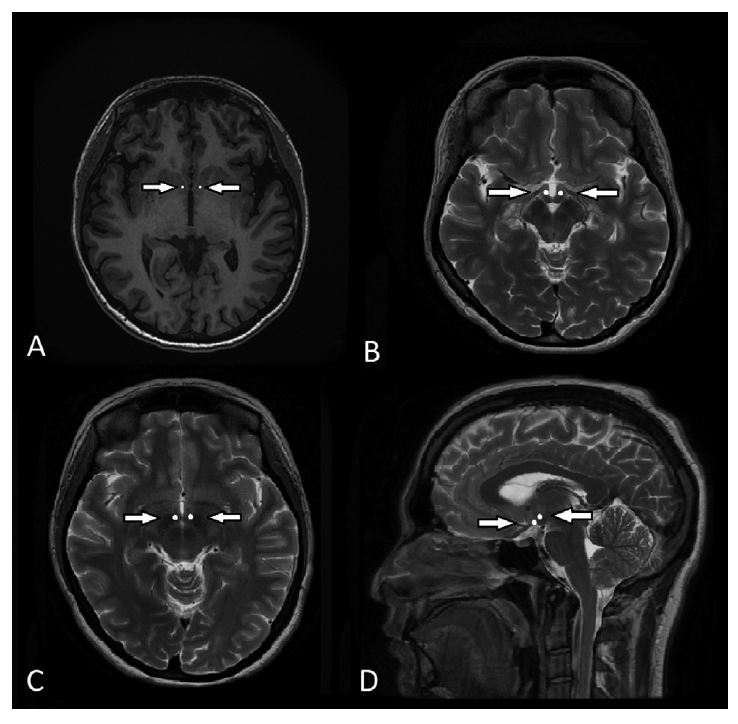

图1:(A) 1.5t MRI T1加权像显示伏隔核(NAc)。NAc使用白点标出。NAc位于内囊的腹侧。(B) 1.5 t MRI T2加权图像上,腹内侧下丘脑(VMH)位于视神经后方,乳头体前方,前连合下方。(C)下丘脑(LH) 外侧分界。LH位于视神经和交叉上方,穹隆下方。(D)矢状位上标记的白点为VMH和LH。VMH位于LH的内侧和腹侧。

DBS已被证明对许多运动障碍,如帕金森病和肌张力障碍疾病非常有效,而且随着在神经精神疾病的治疗中越来越受欢迎,许多研究试图将这种方法也应用于其他疾病。基于目前在肥胖动物模型和人体的研究,DBS主要有3个立体定向靶点:NAc、VMH和LH。NAc是纹状体的一部分,位于内囊前肢下方,视神经上外侧,视前区前方。NAc由主要向边缘系统投射的壳核和向基底神经节投射的核团组成。在动物模型研究中,NAc DBS高频刺激可导致热量摄入限制和体重减轻。VMH是位于视神经后方、乳头体前方、前连合下方的靶点。动物模型研究结果显示低频刺激VMH导致体重和脂肪下降,而高频刺激导致摄食量增加。LH是位于穹窿下方、视神经和视交叉上方的一个小靶点。动物模型研究表明,低频率刺激LH导致黑色素浓缩激素和食欲素的增加,从而诱导食物寻求行为,而高频刺激LH可导致体重下降。